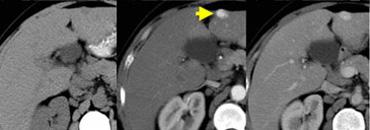

U máu ngấm thuốc nhanh (flash filling) trên thì không tiêm, thì động mạch và thì tĩnh mạch cửa. Lưu ý tỷ trọng tương đương hồ máu.

Các u máu nhỏ có thể biểu hiện ngấm thuốc đồng nhất nhanh chóng (‘flash filling’).

HCC nhỏ và di căn tăng sinh mạch có thể bắt chước u máu nhỏ vì tất cả đều biểu hiện ngấm thuốc đồng nhất trong thì động mạch.

Bằng cách quan sát các thì chụp khác để xem liệu các vùng ngấm thuốc có tương đương hồ máu hay không, thông thường có thể phân biệt được các tổn thương này.